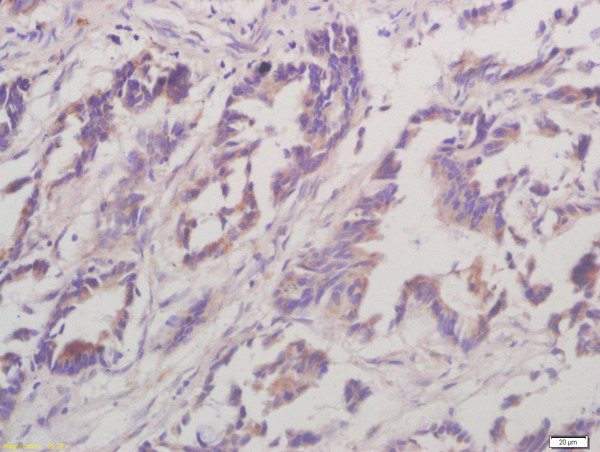

- Main image

- Experimental details

- Formalin-fixed and paraffin embedded human gastric carcinoma labeled with Anti-Caseine Kinase 1 alpha Polyclonal Antibody, Unconjugated (bs-12427R) at 1:200 followed by conjugation to the secondary antibody and DAB staining

- Sample type

- Horse

- Other comments

- Stomach